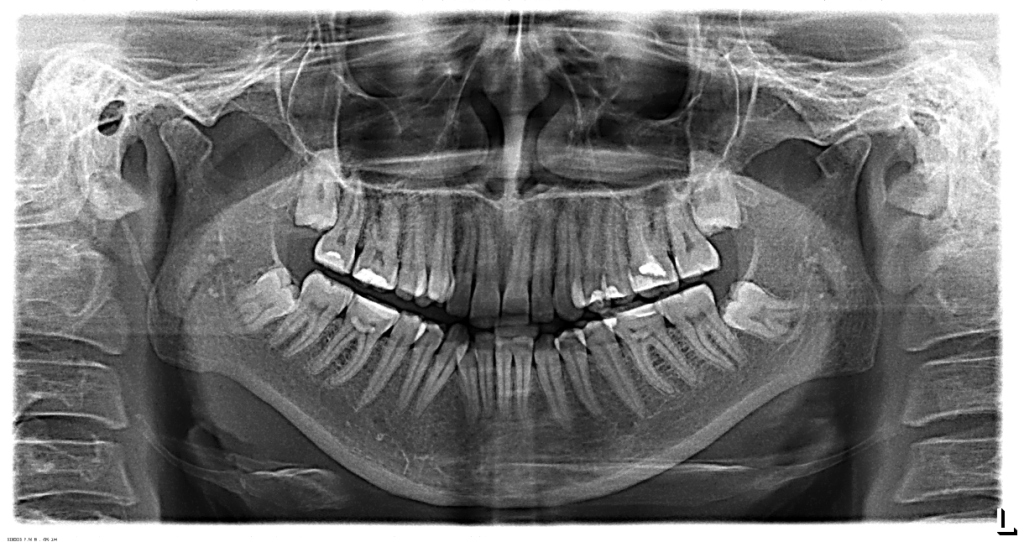

Для установления брекетов врач мне рекомендует удалить верхнюю справа четверку, чтобы поставить на ее место клык, и нижний второй резец справа, аргументируя тем, что так будет быстрее идти лечение, по словам врача корень у этого резца оголен и подвижен (хотя я не чувствую, чтобы он шевелился) и, что все равно в дальнейшем этот зуб я потеряю (и никто, кроме стоматологов не будет замечать, что резцов нижних у меня 3, вместо 4х).

Правда ли то, что этот зуб (резец второй) не здоров? И лучше удалить его, а не 4 нижнюю справа?

По снимку невозможно диагностировать подвижность зуба. Существует методика, при которой возможно удаление и всех восьмых зубов, и, если потребуется, четверок.